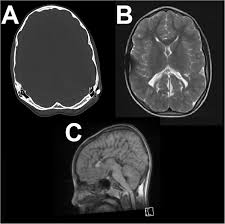

'copper beaten' skull refers to the prominent convolutional markings seen in multiple bones of the skull. Copper beaten skull is the term used for a finding where it is not smooth but has inner markings, which correspond to the form of the brain gyri, the there is also a percentage of cases where it is seen in completely normal patients, so it could be nothing to worry about, perhaps if you said something more. Skull radiograph demonstrates multiple small radiolucent areas with relatively round radiopaque markings around them, in a pattern similar to the at produced by beating on a sheet of metal with a small mallet. The ore is concentrated by froth flotation process. Even today, a lot of jewellery in india is.

Pediatric Radiology from image.slidesharecdn.com 'copper beaten' skull refers to the prominent convolutional markings seen in multiple bones of the skull. Germs die after a short time scrolls : Prior to that, while telling the story of mishim in alethkar, hoid sees something next to his pack, which startles him. Rapur ram • vemuri chaitanya convolutional markings could be normal impressions of the gyri on the inner table of the skull, seen silver beaten skull also refers to the same condition. Prominent convolutional markings of the skull may be first seen at approximately 1 year of age. The significance of digital impressions in children's skulls. However, the copper beaten appearance of the skull has poor sensitivity in detecting increased intracranial pressure as such an appearance can also be seen in normal patients. Copper beaten skull is a phenomenon wherein intense intracranial pressure disfigures the internal surface of the skull.

As described above (and seen in the differential diagnosis case), convolutional changes may be normal if they are confined to the posterior calvaria and are subtle.

The cbk appearance is typically associated. The appearance is called copper beaten skull or brass beaten skull. Skull radiograph demonstrates multiple small radiolucent areas with relatively round radiopaque markings around them, in a pattern similar to the at produced by beating on a sheet of metal with a small mallet. The appearance of a copper beaten skull is associated with raised intracranial pressure in children. If you continue browsing the site, you agree to the use of cookies on this website.

Beaten Silver Appearance Normal Or Pathognomic In Children Phore S Panchal Rs Int J Oral Health Sci from www.ijohsjournal.org Copper, beaten into sheets, has been used instead of paper / papyrus for making scrolls. Beaten copper appearance (hammered silver). Skull radiographs demonstrate copper beaten skull. See our user agreement and privacy policy. A diffuse beaten copper pattern on skull radiographs, along with obliteration of anterior sulci or narrowing of basal cisterns in children under the age of 18 months, is predictive of increased intracranial pressure in over 95 percent of cases tuite and lindquist, 1996. Slideshare uses cookies to improve functionality and performance, and to provide you with relevant advertising. Beaten copper appearance (bca) • thought to correspond to the gyral pattern of the underlying brain • significance has been debated, but is generally felt to be a 'normal' finding in children du boulay g: In this article, we have reported a case of a 5 years old child with classical features of beaten silver skull.

However, the copper beaten appearance of the skull has poor sensitivity in detecting increased intracranial pressure as such an appearance can also be seen in normal patients. Zurück zum zitat mahomed n, sewchuran t, mahomed z. A diffuse beaten copper pattern on skull radiographs, along with obliteration of anterior sulci or narrowing of basal cisterns in children under the age of 18 months, is predictive of increased intracranial pressure in over 95 percent of cases tuite and lindquist, 1996. Beaten copper appearance (hammered silver). Hoid appears as wit in the middle of the novel, discussing the nature of power with shallan. Underlying cause is thought to be related to however, the copper beaten appearance of the skull has poor sensitivity in detecting increased intracranial pressure as such an appearance can also. Copper beaten skull is a phenomenon wherein intense intracranial pressure disfigures the internal surface of the skull. Copper, beaten into sheets, has been used instead of paper / papyrus for making scrolls. Prior to that, while telling the story of mishim in alethkar, hoid sees something next to his pack, which startles him. Copper beaten skull is a phenomenon wherein intense intracranial pressure disfigures the internal surface of the skull. Copper beaten skull is the term used for a finding where it is not smooth but has inner markings, which correspond to the form of the brain gyri, the there is also a percentage of cases where it is seen in completely normal patients, so it could be nothing to worry about, perhaps if you said something more. Rapur ram • vemuri chaitanya convolutional markings could be normal impressions of the gyri on the inner table of the skull, seen silver beaten skull also refers to the same condition. Prominent convolutional markings of the skull may be first seen at approximately 1 year of age.

Hoid appears as wit in the middle of the novel, discussing the nature of power with shallan. A diffuse beaten copper pattern on skull radiographs, along with obliteration of anterior sulci or narrowing of basal cisterns in children under the age of 18 months, is predictive of increased intracranial pressure in over 95 percent of cases tuite and lindquist, 1996. Beaten copper appearance (hammered silver). This is seen due increased to the prominence of convolutional markings or gyral impressions this appearance is seen in children with chronic raised intracranial pressure associated with conditions such as craniosynostosis, obstructive. The cbk appearance is typically associated.

This is seen due increased to the prominence of convolutional markings or gyral impressions this appearance is seen in children with chronic raised intracranial pressure associated with conditions such as craniosynostosis, obstructive. The molten copper is poured out and allowed to cool. If you continue browsing the site, you agree to the use of cookies on this website. 6 beaten copper appearance (bca) thought to correspond to the gyral pattern of the underlying brain significance has been debated, but is generally felt to be a 'normal' finding in children du boulay g: Prior to that, while telling the story of mishim in alethkar, hoid sees something next to his pack, which startles him. Zurück zum zitat mahomed n, sewchuran t, mahomed z. The appearance is called copper beaten skull or brass beaten skull. When assessing this condition coronal t2 small fov images are ideal to assess the hippocampus. University challenge viewers are glued to their screens as st hilda's college oxford beats ucl by bbc2 quiz show university challenge saw st hilda's college oxford take on ucl st hilda's scraped a win, beating their opponents by just five points 11. Even today, a lot of jewellery in india is. Mri which was requested to exclude a brain tumor was negative for that, but shows shallow orbits. Slideshare uses cookies to improve functionality and performance, and to provide you with relevant advertising. The significance of digital impressions in children's skulls.